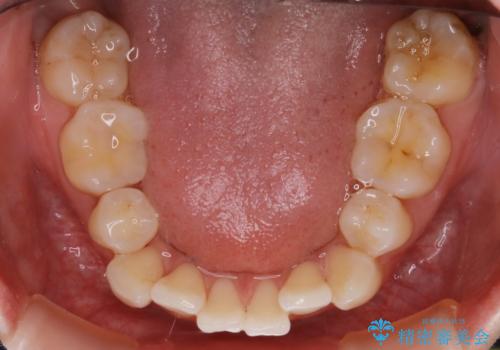

- 以前、中学生から高校生にかけてワイヤー装置による抜歯矯正を経験されている患者さんで、大人になってからのライフスタイルの変化でリテーナーを継続使用することができず、ガタつきが目立つようになってきてしまったのでもう一度矯正治療がしたいという主訴でご来院されました。

既に上下左右の4番目の歯が抜歯されているため、今回の治療では抜歯をせず歯の移動だけでガタつきを治す必要があり難易度が高くなっていました。